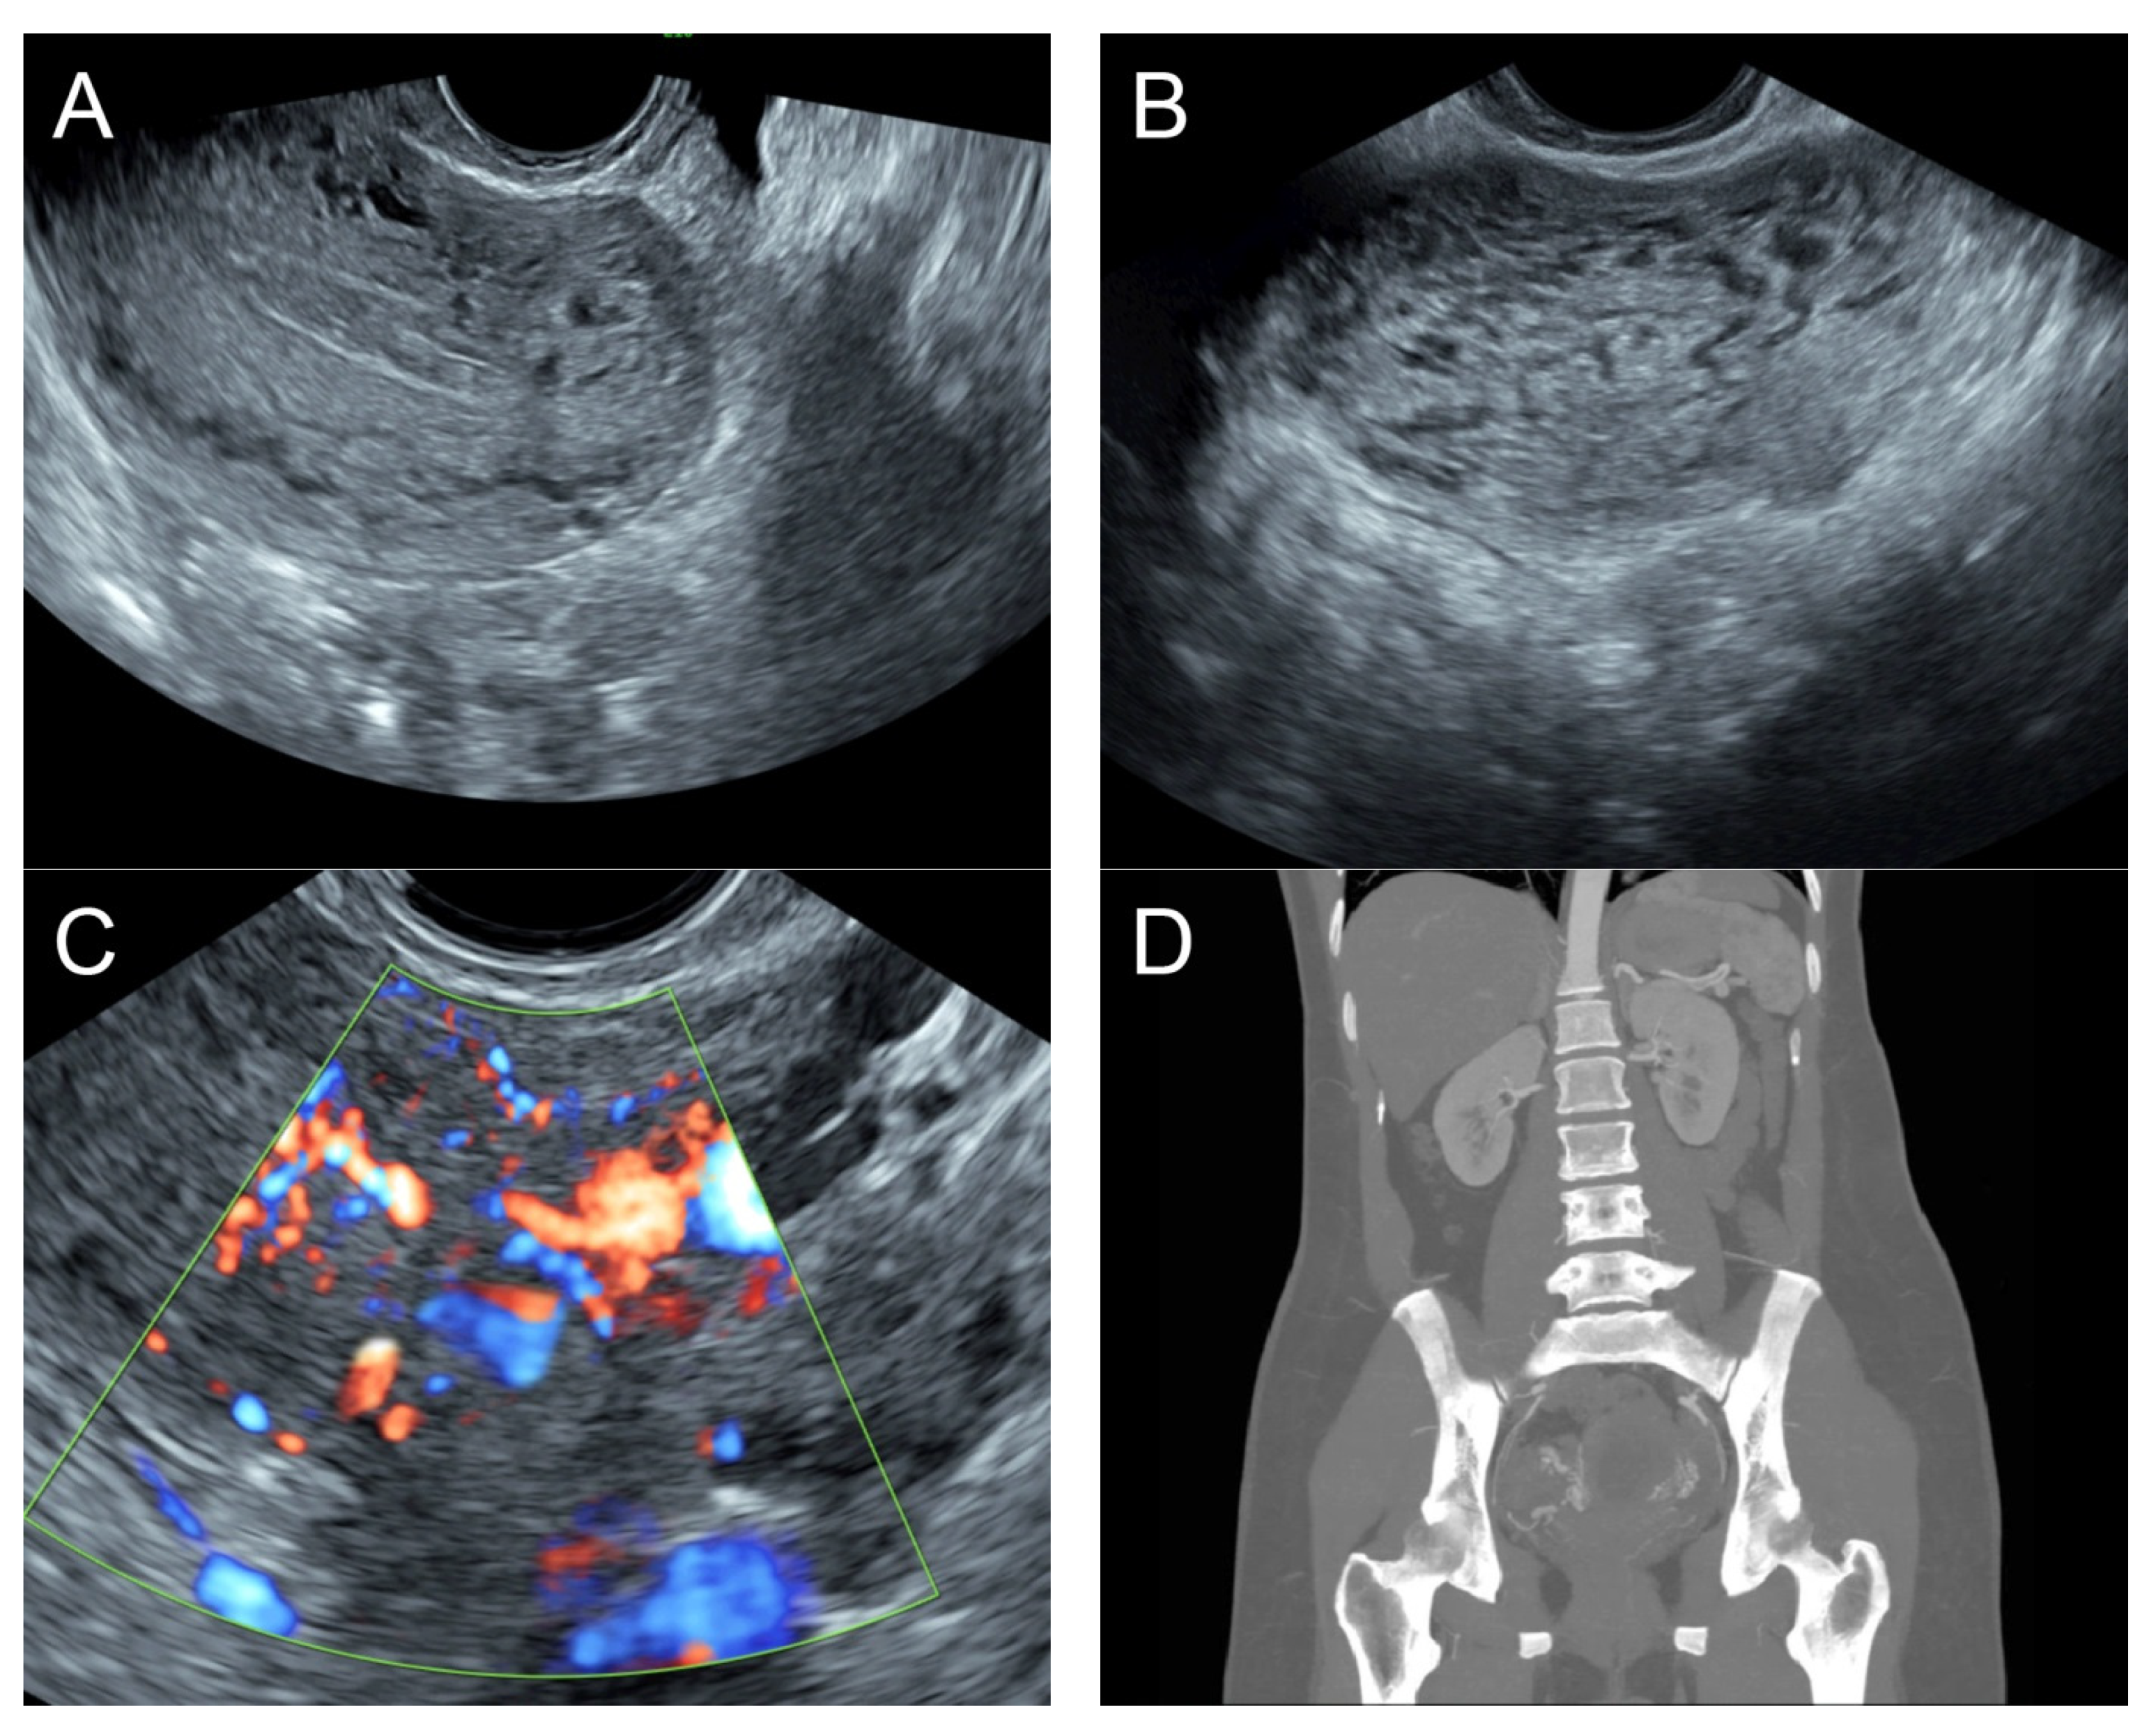

Figure 6. (A) Transvaginal ultrasound: sagittal scan of the uterus showed heterogeneous echoes of the myometrium; a dilated arcuate artery at the posterior wall; several small anechoic/hypoechoic spongy structures within the myometrium, mainly at the anterior wall; no other specific lesions of the uterus. The endometrium appears normal. (B) Cross-sectional scan of the fundus showed several small anechoic/hypoechoic tubular structures or a spaghetti-like appearance throughout the myometrium. (C) Color flow mapping showed hyper-vascular areas in the myometrium, without well-defined lesion borders; multidirectional flow mainly localized at the anterior wall. The main differential diagnosis was adenomyosis or gestational trophoblastic disease. (D) Abdominal CTA revealed hypervascularity and tortuous arterial anatomy enhancing dilated vessels of the uterus, with bilateral uterine arteries as the feeding arteries, confirming uterine AVM.